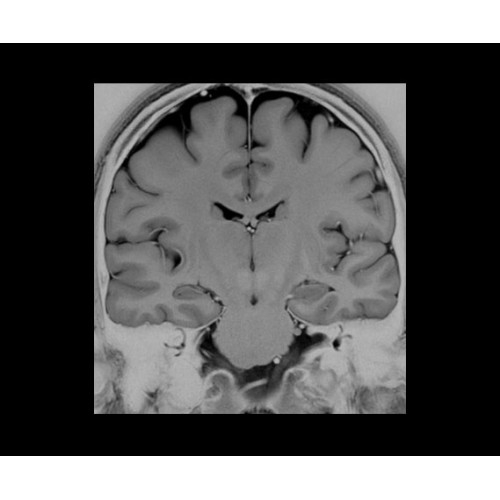

SIGNA PET/MR 3.0T — это гибридная система, в которой совмещаются две принципиально разные технологии — магнитно-резонансную томографию (МРТ) и позитронно-эмиссионную томографию (ПЭТ). Система отличающийся высокой чувствительностью и эффективностью и предназначена для диагностики в области онкологии, неврологии, кардио-васкулярных исследований, исследований воспалительных процессов.

Компания GE Healthcare представляет революционную, полностью интегрированную систему SIGNA PET/MR1, в которой сочетаются времяпролетная технология (TOF) и возможности напряженности магнитного поля 3.0 Тл. Мы поможем вам поднять исследования на более высокий уровень. SIGNA PET/MR позволяет достичь впечатляющей точности и скорости исследований, а благодаря новейшей технологии реконструкции Q.Clear2 качество изображений улучшается в два раза. Кроме того, в систему включен полный набор клинических приложений и гибких катушек для проведения любых видов исследования, открывая для вас возможности визуализации, о которых вы даже не догадывались.

Кроме того, в результате использования технологии TOF и инновационной технологии реконструкции Q.Clear вы сможете добиться прекрасного соотношения сигнал/шум. А благодаря технологии нулевого времени эхо (ZTE) визуализировать костную структуру без ионизирующего излучения. Все эти разработки для улучшения качества сканирования и точности анализа помогут вам использовать весь потенциал ПЭТ/МРТ.

• МРТ с функцией нулевого времени эхо (ZTE) отличается точностью, возможностью персональных настроек и отсутствием ионизирующего излучения. Она приходит на смену традиционному исследованию на основе рентгеновского излучения. МРТ с функцией нулевого времени эхо (ZTE) на базе SIGNA ПЭТ/МРТ является более надежной и быстрой по сравнению с системами, использующими сверхмалое время эхо (UTE).